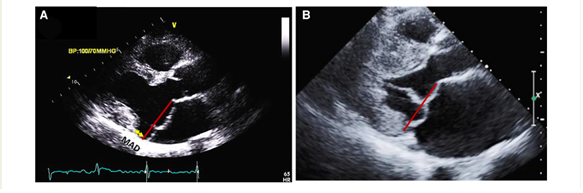

The presence of MAD should be detected as well. It may manifest at various locations on the mitral annulus, but it carries an increased risk of VAs when observed at the posterior LV wall. Occasionally, MAD is associated with a distinct mid-systolic to late-systolic spike on the lateral mitral annulus, as detected by Doppler. To measure MAD's length, the parasternal long-axis view at end-systole is employed, defining it as the distance between the mitral annulus and the systolic bulge of the ventricular myocardium (typically ranging from 5–10 mm in long-axis view) (5,6).

Figure 1 - How to assess mitral valve prolapse and mitral annular disjunction.png

As for echocardiography, it is imperative to document key mitral valve characteristics, including bileaflet MVP and myxomatous MVP. The assessment should encompass measurements of the mitral annulus at both end-systole and end-diastole in both anteroposterior and inter-commissural aspects. Additionally, factors such as leaflet diastolic thickness, leaflet length, prolapsed distance, and the presence or absence of systolic curling, if applicable, should be mentioned, and quantification is necessary (8).

A comprehensive evaluation of MAD around the mitral annulus involves acquiring six left ventricular long-axis cine sequences with a 30° interslice rotation. Assessing MAD severity typically requires measuring its longitudinal length, at least from the long-axis view, and possibly its circumferential extent expressed in degrees (8,9,10).